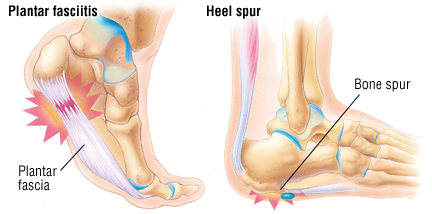

Heel Spurs – Feebo PLANTAR FASCIITIS (HEEL PAIN) - UDAI

PLANTAR FASCIITIS (HEEL PAIN) - UDAI  Heel Pain | Plantar Fasciitis Causes

Heel Pain | Plantar Fasciitis Causes  Plantar Fasciitis and Heel Spurs

Plantar Fasciitis and Heel Spurs  Plantar Fasciitis vs. Heel Spurs | Heel

Plantar Fasciitis vs. Heel Spurs | Heel  Plantar Fasciitis/Heel Pain Reasons

Heel Spur Pain Also Called Calcaneal  Heel Spur VS Plantar Fasciitis

Heel Spur VS Plantar Fasciitis  10 Heel Pain Causes And When To See a